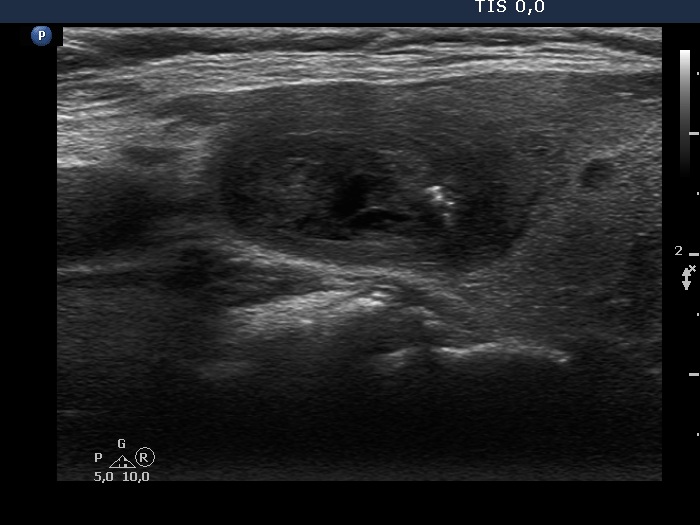

Ultrasonography. The thyroid was echonormal. There was a mixed moderately hypoechogenic-cystic nodule in the right lobe. The lesion presented various intranodular hyperechogenic granules including back wall figures, non-specific granules and a few typical comet-tail artifacts. There were other, difficult-to-classify bright granules. The latter could be either comet-tail artifacts or microcalcifications. There were several moderately hypoechogenic lesions in the left lobe.

Comments. This case illustrates the difficulty of distinguishing comet-tail artifact from microcalcification. The relevance of this differentiation lies in the consequences, the former is found almost always in benign lesions while the presence of microcalcifications increases the likelihood of papillary carcinoma.